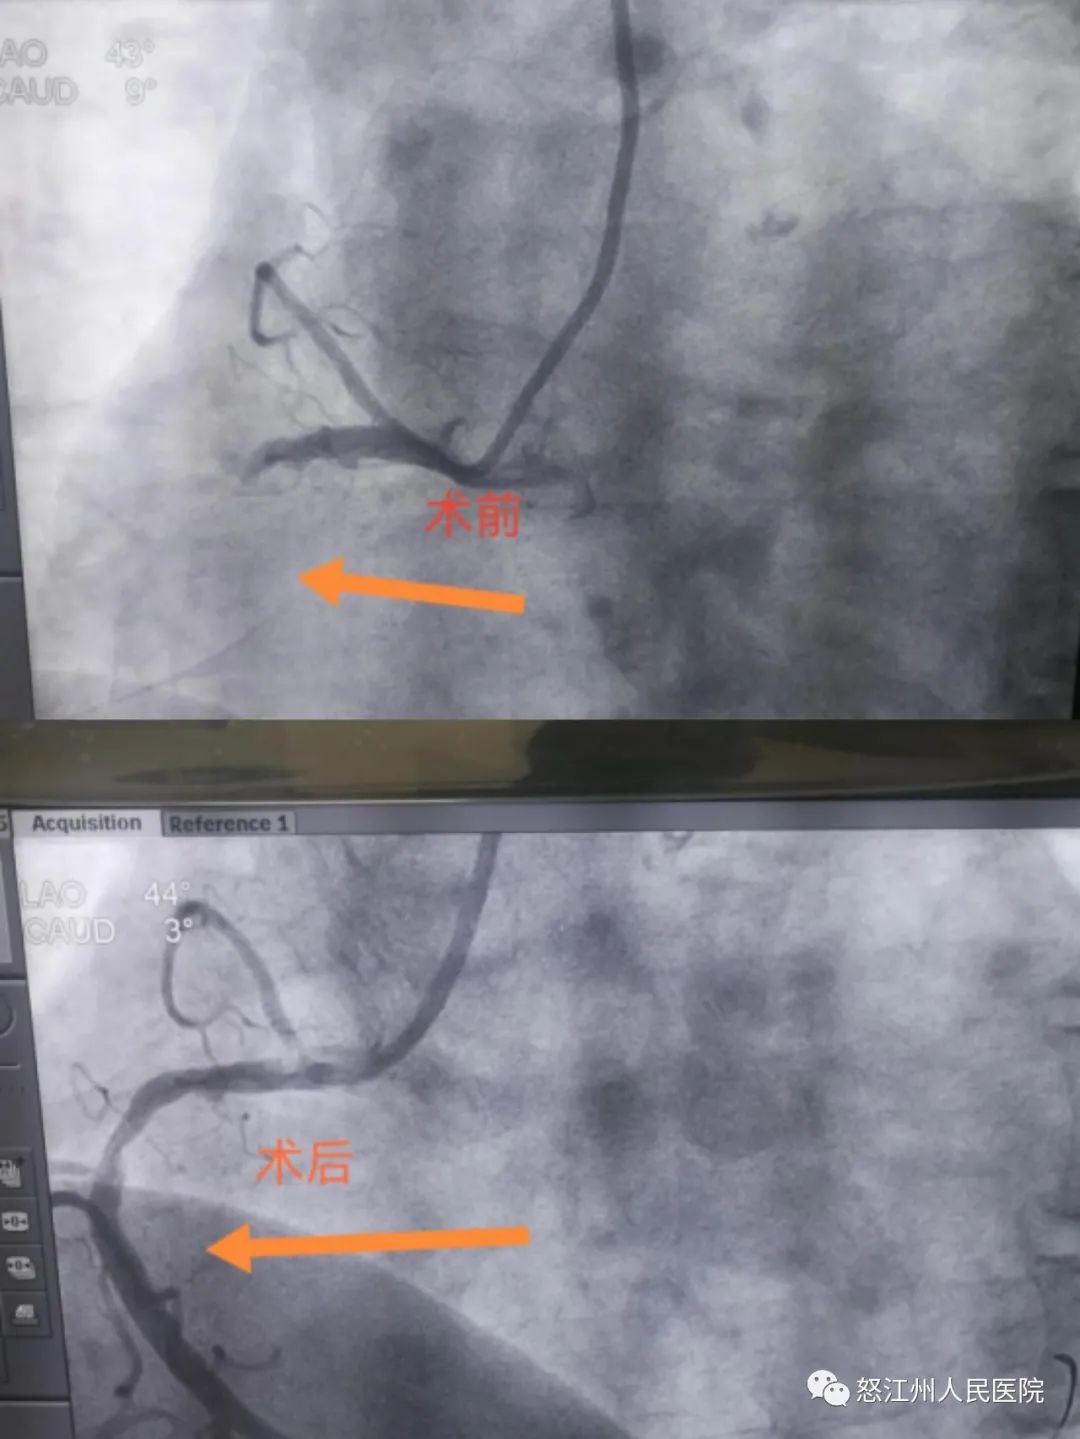

患者51岁的张先生,10月16日晚20时,因酒后出现胸痛,呈胸骨后持续性压榨样疼痛,伴后背部放射痛、大汗淋漓等症状,于21:42分由家属送至泸水市人民医院就诊,经心电图检查提示诊断为急性ST段抬高型心肌梗死,值班医生立即给予双抗负荷对症治疗,同时将情况上传至怒江州胸痛中心绿色通道微信群。

怒江州人民医院胸痛中心迅速做好接诊准备,立即启动绿色通道,22:05分泸水市第一人民医院医护人员转送患者,22:18分救护车到达我院大门。早已在等候的相关科室医生迅速将病人送至导管室,进行介入治疗。22:51分导丝通过梗塞冠脉,患者转危为安。